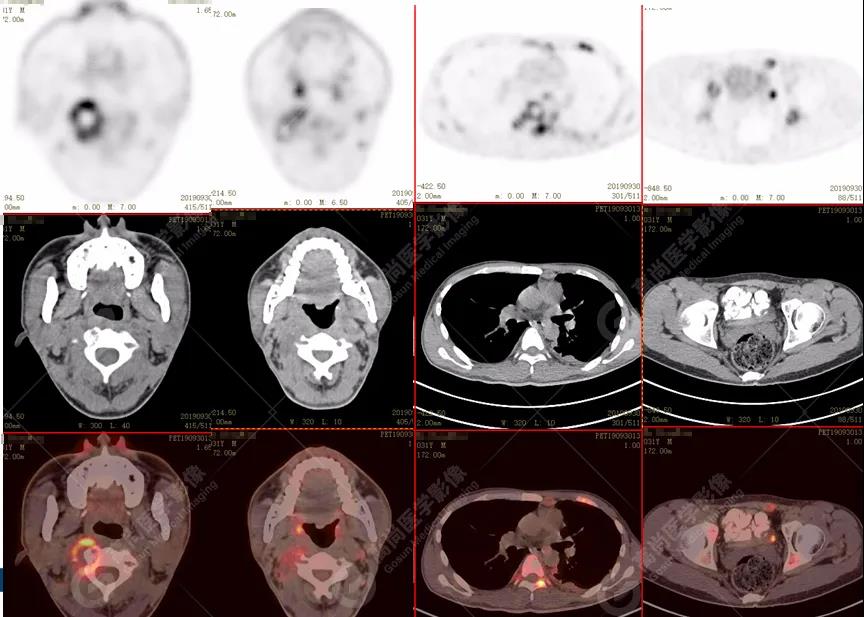

全身多發(fā)高代謝腫大淋巴結,中央代謝缺損

左側胸膜結節(jié)樣增厚,代謝不同程度增高

特征:肺部病灶簇狀分布,上葉尖段及下葉背段為著;腫大淋巴結分布不對稱,無融合、中央有壞死改變,與淋巴瘤、轉移瘤等有一定的鑒別診斷意義;

淋巴結結核:常伴壞死,壞死區(qū)相對邊界較清楚,淋巴結之間無融合;